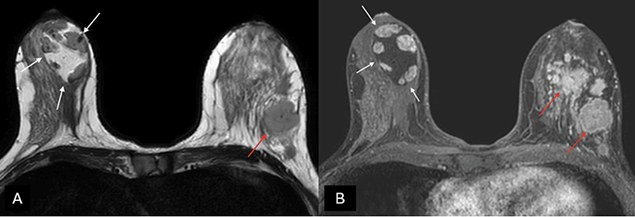

MRI can be useful in establishing a diagnosis if suspicious features are noted on mammography or ultrasound [27]. Otherwise, MRI is not generally indicated for typical MH. On T1- and T2-weighted sequences (Figure 4), hamartomas appear as heterogeneously intense masses with glandular and fatty tissue components and a thin capsule [24]. Once the contrast media has been administered, MH exhibits a gradual, progressive enhancement with a type I time/intensity curve [28].

Figure 4. (A) Axial T2-weighted images and (B) T1-weighted fat-suppressed enhanced magnetic resonance imaging (MRI) – a capsulated, large-sized hamartoma can be seen located in the outer quadrants of the right breast, exhibiting a signal identical to normal mammary gland tissue, creating a “breast within a breast” appearance (white arrows). There are multiple masses in the contralateral breast with suspicious morphology, associated with a known invasive ductal carcinoma (red arrows). Image credits: El Yousfi Z, El Mansoury FZ, El Bakkari A, Omor Y, Latib R. Breast hamartoma with synchronous contralateral breast cancer: a case report. Cureus 2024; 16(8): e66534. DOI: 10.7759/cureus.66534. Reused under the terms of the Creative Commons Attribution License CC-BY 4.0. (https://creativecommons.org/licenses/by/4.0/deed.en).